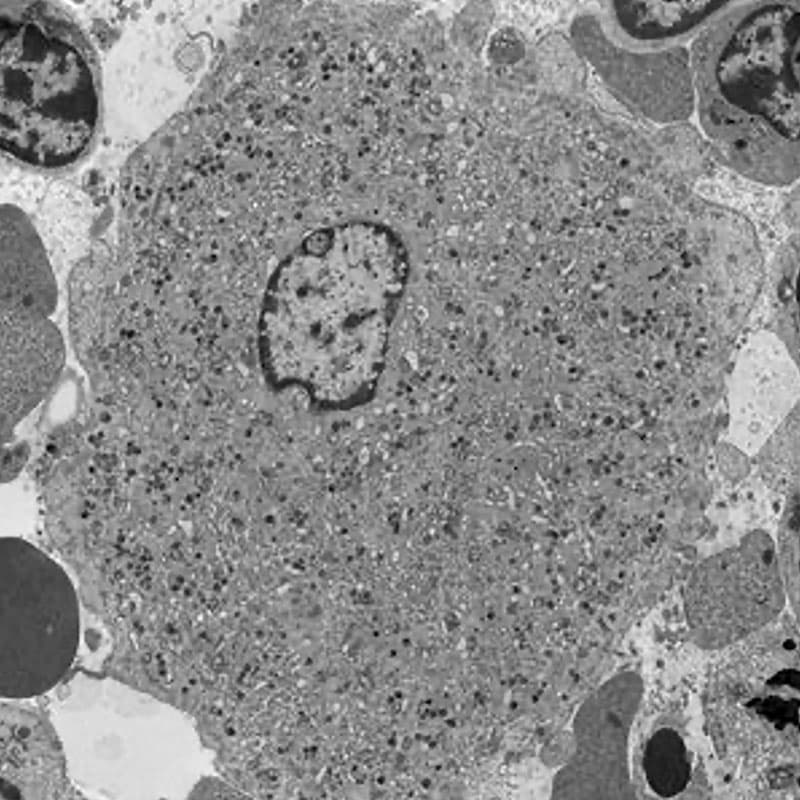

Fig.1. Transmission electron microscopy of a mouse bone marrow megakaryocyte.

Blood platelets are produced in the bone marrow by megakaryocytes in unique processes that require polyploidisation and extensive membrane rearrangements. These include the formation of the demarcation membrane system, the surface-connected membrane reservoir for future platelets. As megakaryocytes mature, the demarcation membrane system initiates as a single plasma membrane invagination that extends between the lobes of the polyploid nucleus and further expands into its mature form by addition of intracellular membrane materials that are biosynthesized in the endoplasmic reticulum or transported from the Golgi apparatus. The precise molecular mechanisms responsible for these unique membrane rearrangements remain poorly understood. Our current research is focused on the role of receptor-mediated endocytosis in platelet production and function, focusing on the F-BAR protein PACSIN2 and the large GTPase dynamin 2.